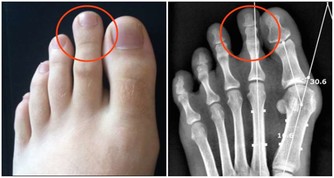

免疫力下降的7個報警信號

1、經常感到疲憊,無精打采;

2、容易反复感冒,尤其是換季時節,且患病時間較長;

3、傷口癒合緩慢;

4、容易患上胃腸疾病;

5、口腔潰瘍反復發作;

6、皮膚容易出現過敏、濕疹等皮膚問題;

7、經常咳嗽,或支氣管、肺部等發炎;

以上7條,如果符合3條及以上,可能預示免疫力下降。